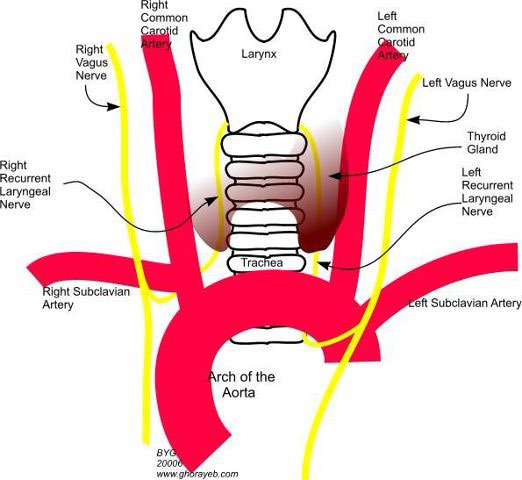

CN X

- common carotid a. 外側,蓋在 thyrocervical trunk 上

- recurrent laryngeal n.沿 tracheoesophageal groove 攀升(就是食道和氣管中間),接觸 medial thyroid gland,向內鑽到 inf. constrictor,進入 larynx,同時支配感覺與運動

- Recurrent laryngeal n.

- 過Cricothyroid joint改叫Inf. laryngeal n.

- 支配所有軟骨間肌,除了 Cricothyroid m.

- 假聲摺以下的喉部黏膜感覺

recurrent laryngeal n.

- left: arch of aorta

- right: Subclavian a.